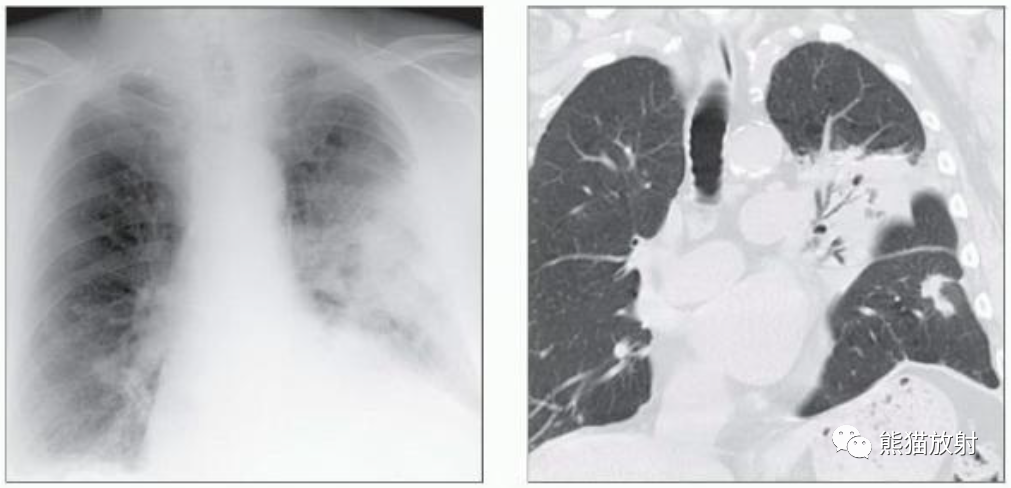

(左)急性髓细胞性白血病和侵袭性曲霉病患者,轴位NECT显示多个肺结节,一些有空洞(直箭),周围有磨玻璃影。其中一个结节中的空气新月征(弯箭)勾勒出局部肺坏死,这是血管侵袭性真菌感染的特征。

(右)图示为侵袭性曲霉病的典型特征,特征是多灶性空洞性病变,可见空气新月形征包围的坏死肺和周围出血所致的晕征。

(左) 50岁男性,HIV感染并大咯血。胸片显示左肺上叶肿块,边缘不规则,其内局部透亮度增高,提示空气新月征。

(右) 同一患者,轴位CT显示厚壁空洞病变,中央见不均匀软组织密度灶,周围见磨玻璃影及小结节。术后诊断为侵袭性曲霉菌病。